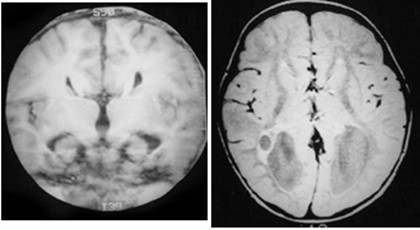

Figure 2

Clinical and image aspects of patient 2

Figure 3

Clinical and image aspects of patient 3